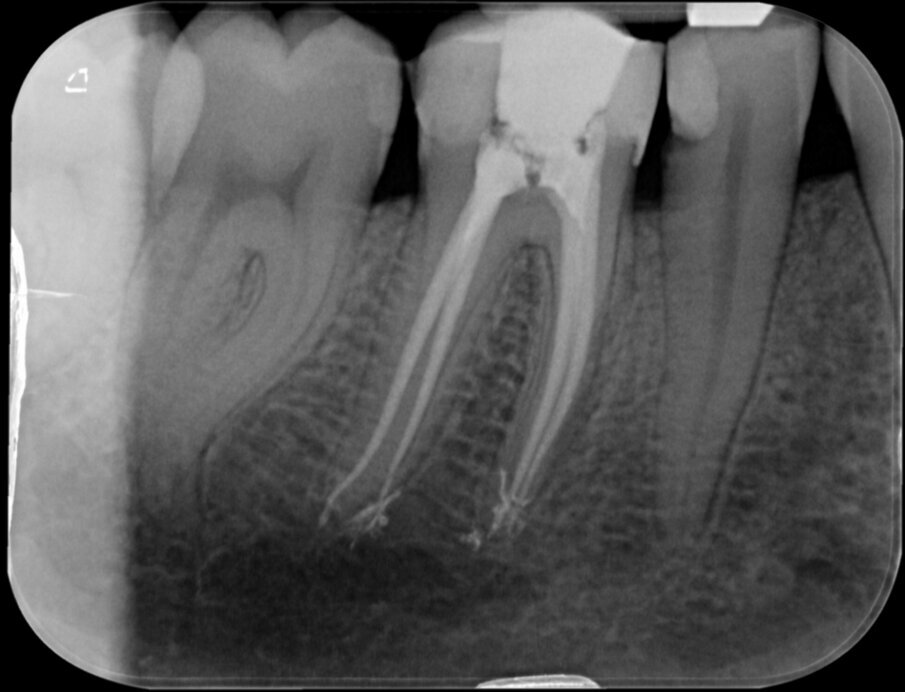

Vier jaar geleden meldde zich een patiënt in onze praktijk met heftige pijn in de regio 46. Na een blik op de bitewing en op de apicale röntgenopname (afbeelding 1 en 2) is de indicatie endodontische behandeling 46 snel gesteld.

De lengte van de kanalen was ongeveer 25 millimeter. Na openen en toegang verkregen te hebben tot het bovenste 2/3 gedeelte van de radix werd het apicale deel van de kanalen benaderd met behulp van SS K-vijlen 08 en 10. We maakten de kanalen doorgankelijk (‘patent’, een term van professor Herbert Schilder) en maakten het kanaal zodanig glad dat we een nieuwe rechte K-vijl zonder te manoeuvreren moeiteloos op de door de elektronische lengtemeter vastgestelde lengte kunnen laten glijden.

De eindfoto’s stemmen tot optimisme. Röntgenologisch lijkt voldaan aan al de eisen die Schilder aan de vorm van geprepareerde kanalen stelde.

Er lijkt sprake van een gevuld systeem (afbeelding 3 en 4). De puffs in de laatste paar millimeter hebben geen klinische betekenis, maar zijn een normaal bijverschijnsel bij het obtureren van kanalen met een hydraulische obturatiemethode, gebruik makend van warme guttapercha. Hier kozen we voor Thermafil, wat een uitstekende reputatie heeft en de preferente vulmethode is van veel eminente clinici, zoals Buchanan en Ruddle. Vol vertrouwen presenteren we de resultaten aan de patiënt en we schrijven een brief aan de verwijzend tandarts dat het vervaardigen van een kroon nu kan geschieden zonder onaanvaardbare risico’s.